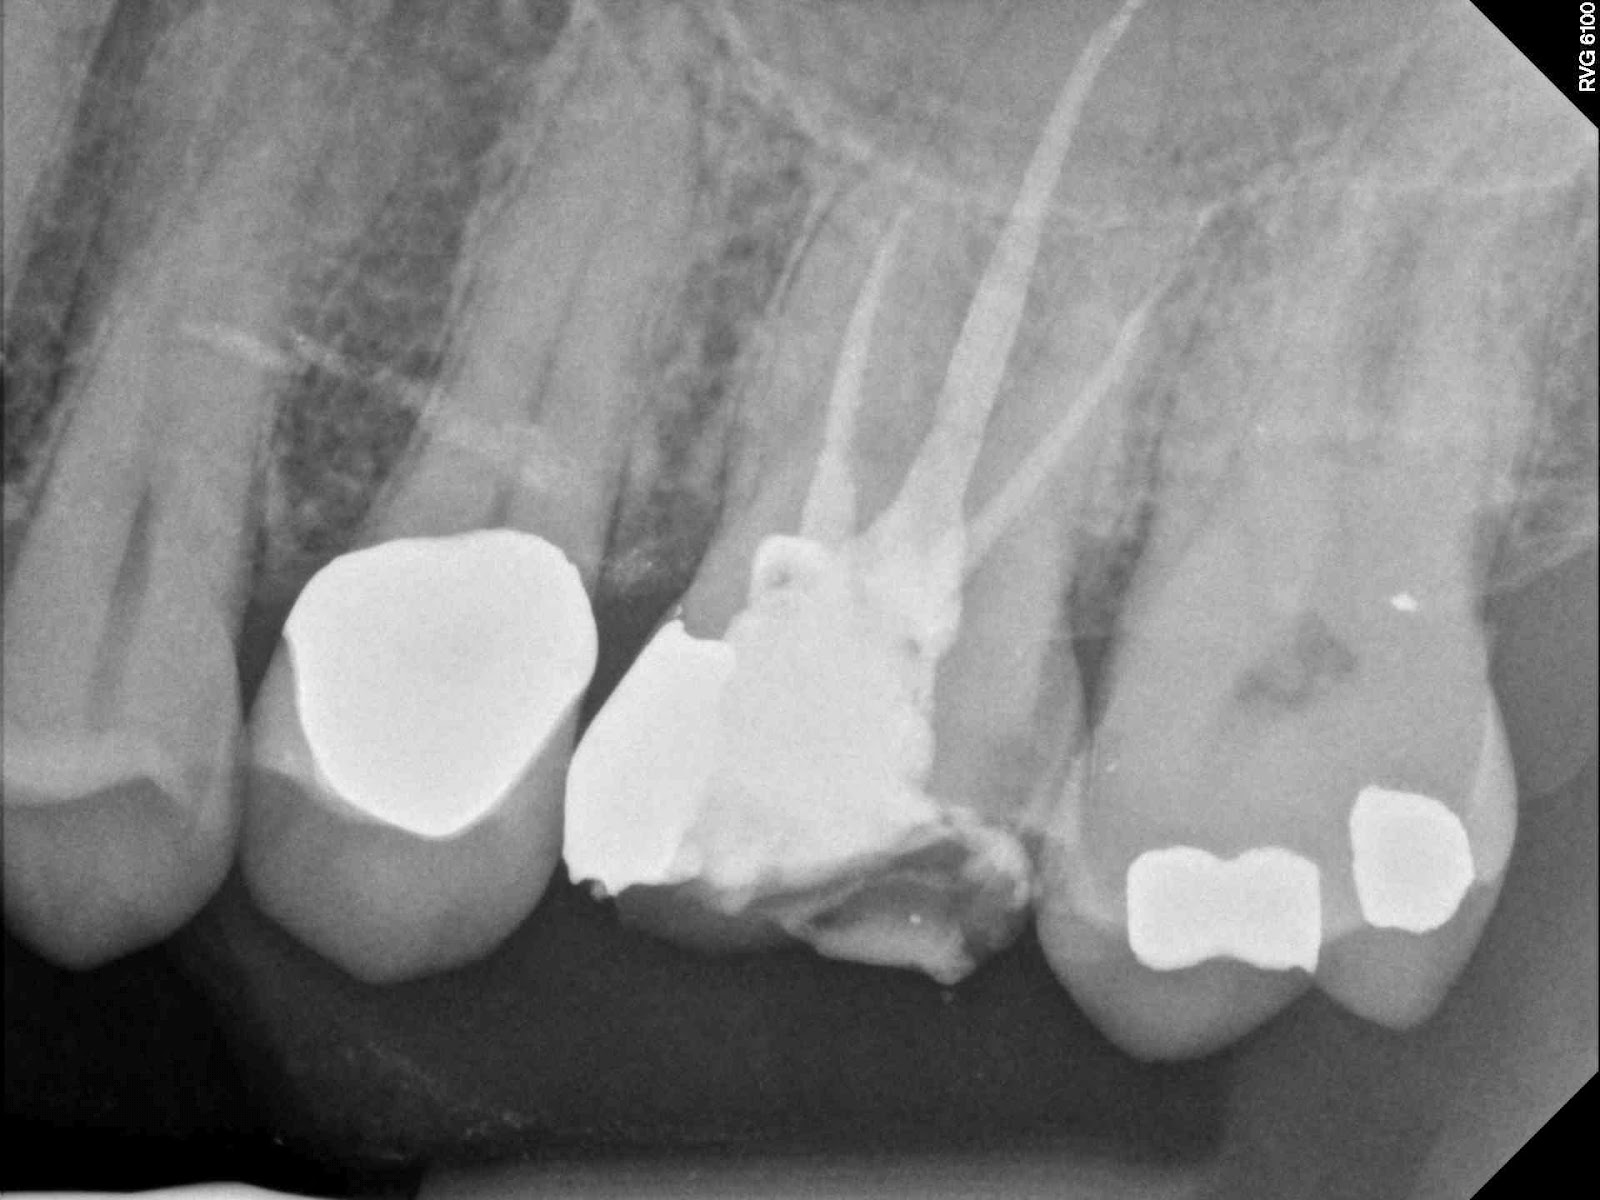

| Pre-op |

| Final no radiographic evidence of MB2 |

| Troughed more with piezo today. No MB2 present |